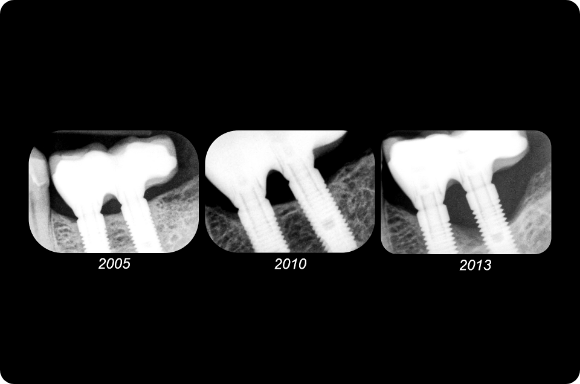

This mastery-level course discusses both the prevention and management of surgical and restorative complications. Within the surgical realm, the presentation focuses on early implant failure and later peri-implant disease. Prosthetic concepts will involve preventative prosthesis design, screw/abutment removal, and sequencing that acknowledges the importance of patient experience.

The implant curriculum is an interactive, procedure-based series of courses that use individual cases to teach current implant treatment. This approach is in contrast to conventional dental education that focuses more on didactic topics and theory. The purpose of using this educational approach is to highlight the patients and procedures found in everyday clinical practice, where the most important concepts are observed and discussed in multiple clinical scenarios.